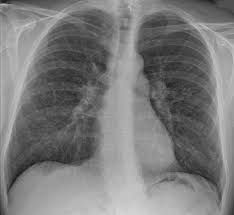

Sarcoidosis is a disease characterized by the growth of tiny collections of inflammatory cells (granulomas) in any part of your body — most commonly the lungs and lymph nodes. But it can also affect the eyes, skin, heart and other organs. The cause of sarcoidosis is unknown, but experts think it results from the body's immune system responding to an unknown substance. Some research suggests that infectious agents, chemicals, dust and a potential abnormal reaction to the body's own proteins (self-proteins) could be responsible for the formation of granulomas in people who are genetically predisposed.